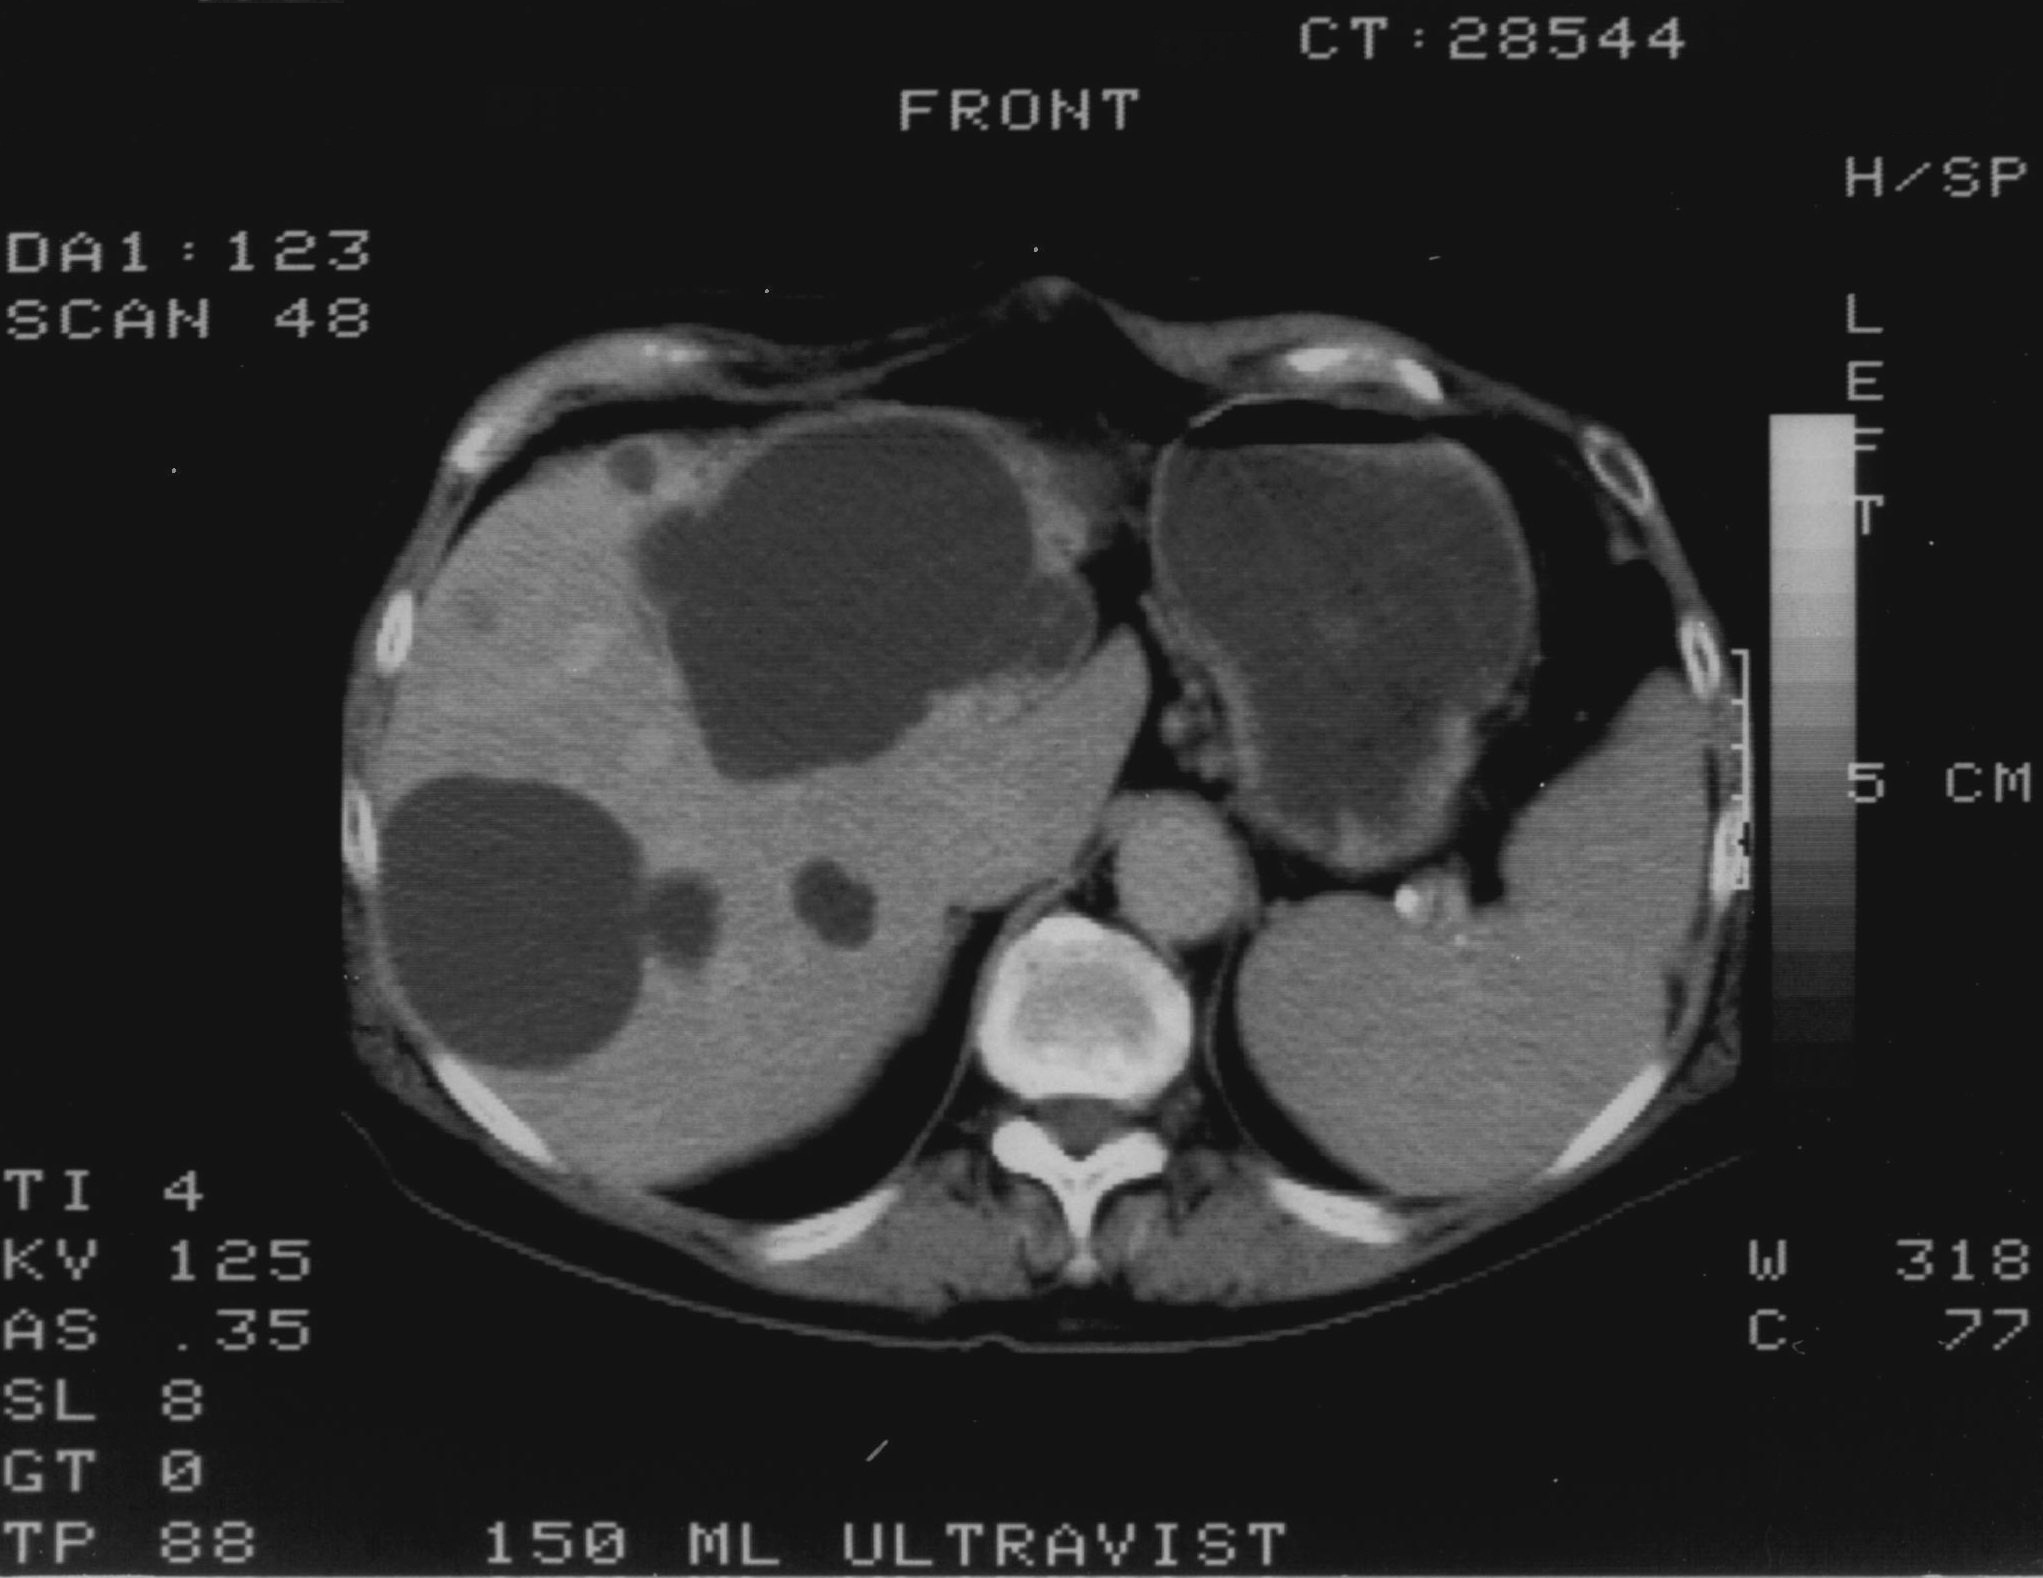

Compared to the surgical methods of past, nowadays these cystic lesions can be successfully treated percutaneously with alcoholic cyst sclerotization. (Figures 26., 27.).

Figure 27. – US and CT examinations before percutaneous ethanol sclerotization (A: US examination, B: CT examination)

The puncture of the cyst is usually guided with US (rarely with CT). The puncturing needs to take place from the parenchymal side of the cyst. When its contents are removed the empty cavity is filled up with diluted contrast material to ensure that there is no contrast leakage to the surroundings. The 96% ethanol is only injected after the contrast material has been removed and no leakage was found. (The volume of the alcohol should not exceed 50-60% of the cyst or 100 ml.)

The injected ethanol is left in the cyst for 20 minutes. Following this, the alcohol is drained as well. Cystic regression is then regularly controlled with US or CT examinations. (Figures 28., 29.) Patient complaints usually cease within 4-6 weeks after the treatment.